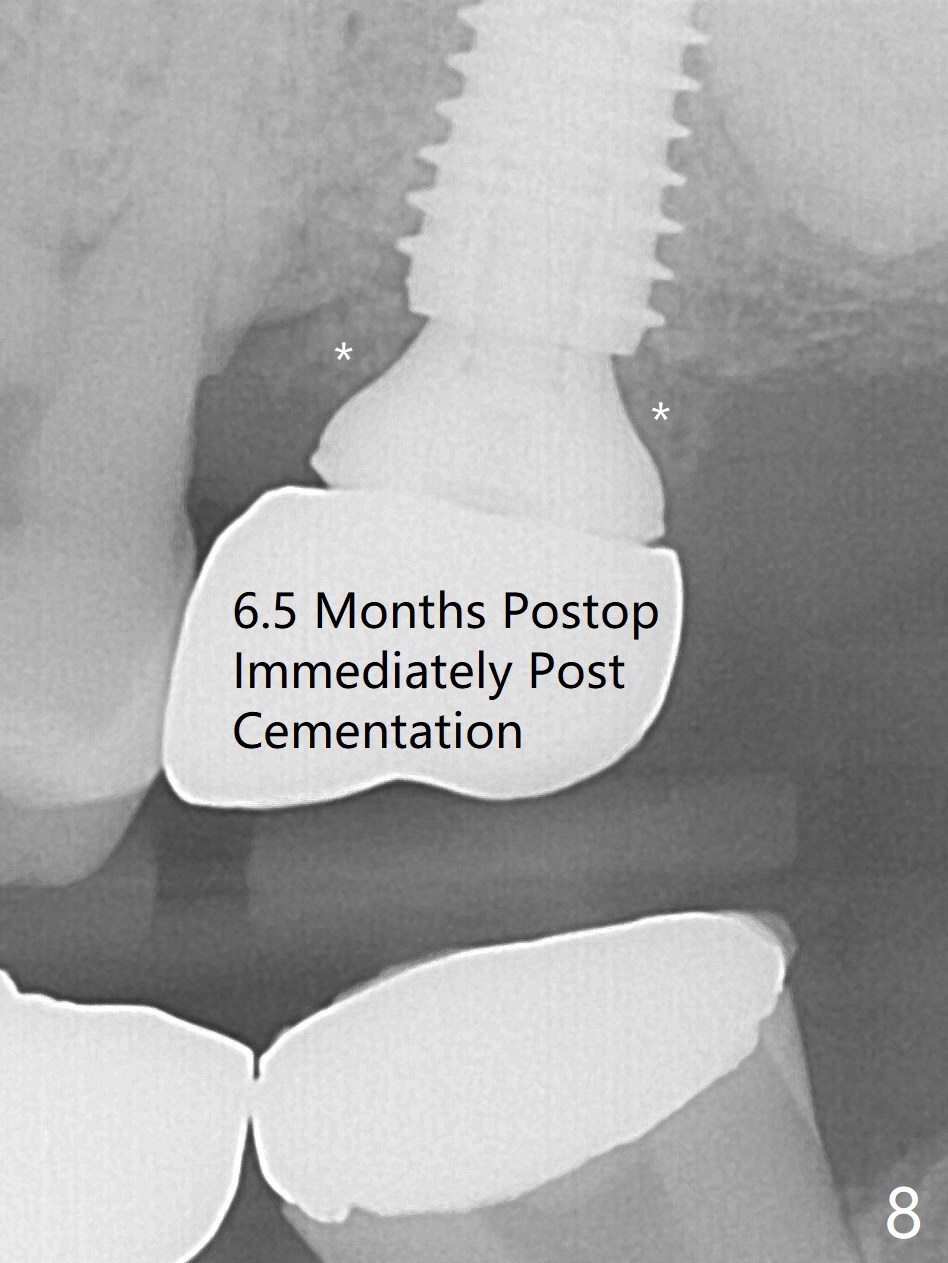

Extraction of the tooth #15 with short clinical crown (suggesting bruxism, Fig.1) reveals a vertical root fracture (Fig.2 <). It seems unnecessary and difficult to create osteotomy in the mesial slope. What can be done is to place starter and 2 mm drills as mesial as possible (Fig.3 (red dashed line: sinus floor). After use of Lindamann bur to move the osteotomy mesially and sequential osteotomy until 3.8x18 mm, a 4.5 mm tap is inserted with clearance from the impacted tooth #16 (Fig.4). A 5x15 mm implant is placed with >60 Ncm with clearance from the 3rd molar (Fig.5,6). If the impacted tooth were removed, the primary stability is expected to be reduced. Impression is taken 6 months postop with 19/20 implants (Fig.7). The bone graft remains in the crestal area immediately and 11 months post cementation (Fig.8,9 *). In the other word, new crestal bone forms after extraction.